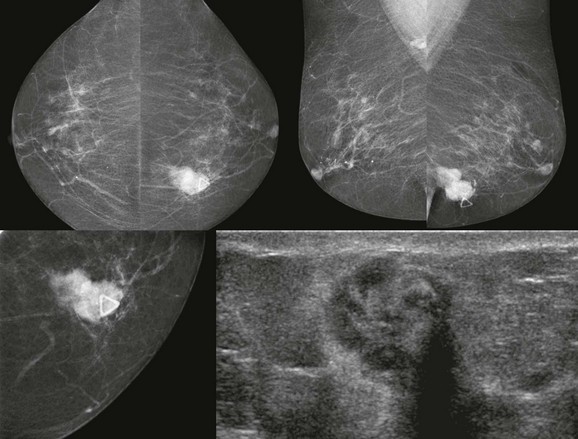

Medullary carcinoma is a very rapidly growing cancer that typically presents as a palpable mass in young or middle-aged women (Fig. 11-6). The median age of diagnosis is 51. “Medulla” means marrow. Like basal cell (triple negative) IDC, medullary carcinoma is characterized by a brisk lymphocytic response, absence of fibroglandular differentiation, and pleomorphic nuclei. There is usually little or no associated DCIS. So at first glance under the microscope medullary carcinoma resembles an aggressive IDC. There is considerable interobserver variability in the pathologic diagnosis of medullary carcinoma that may explain the variable patient outcomes reported across different series. The prognosis for women with this cancer is better than for typical IDC in most series.

FIGURE 11-6 Medullary Carcinoma.

This 44-year-old woman presented with a palpable mass (triangle) that corresponds to an oval, relatively circumscribed, high-density mass. US demonstrates a hypoechoic, solid, oval mass with posterior acoustic shadowing.

On mammography, medullary carcinoma typically presents as a round or oval, circumscribed mass without calcifications. It is often palpable.